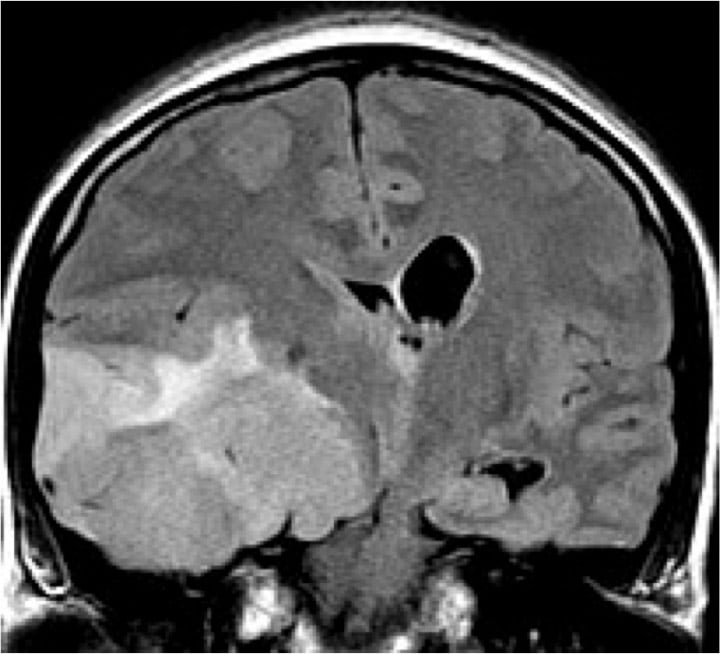

- Brain and spine tumors